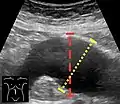

Aortic measurement on abdominal ultrasonography in the axial plane between the outer margins of the aortic wall[37]

Ultrasonography in the sagittal plane, showing axial plane measure (dashed red line), as well as maximal diameter (dotted yellow line), which is preferred